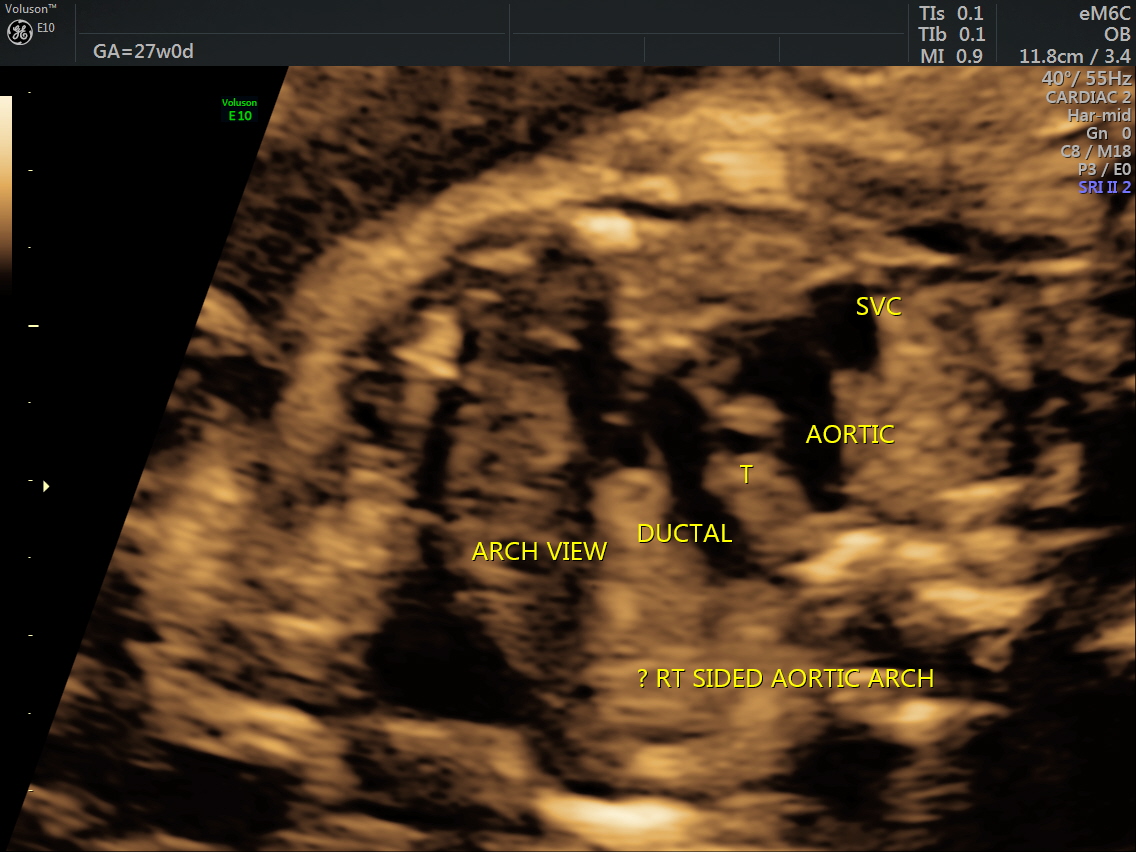

RT AORTIC ARCH_31 Published June 17, 2016 at 1136 × 852 in Rt aortic arch and aberrant left subclavian artery ← Previous Next →